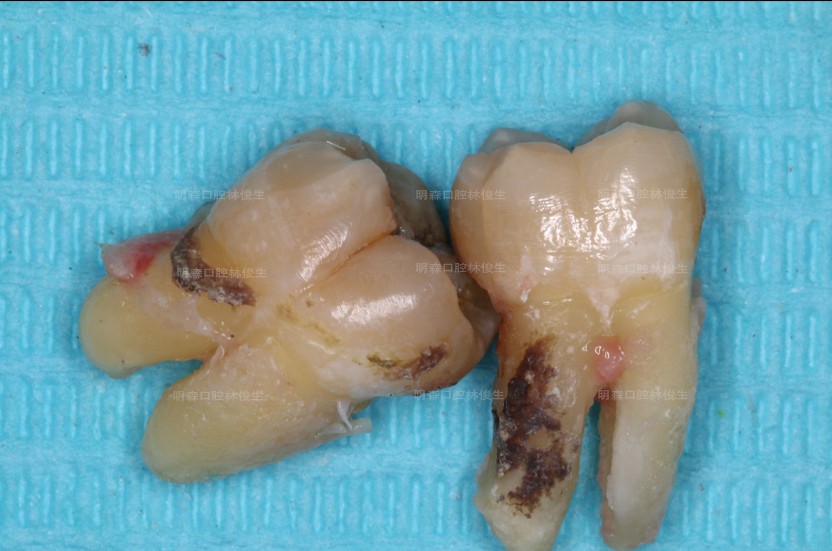

智齿发炎不拔会带来什么后果?我遇到这样一位患者他下颌47远中被智齿“吃了一小块”,导致口腔反复发炎,最后智齿与被“吃了一块”的邻牙一并拔除,最终患者只能通过做种植牙恢复咬合功能。

由于智齿的生长位置、大小、形状的不同,对口腔造成的局部炎症反应或机械性损伤都不尽相同,具体我以本次接诊的患者病症为例。

该患者属于远中阻生齿,牙冠向远中(下颌升支方向)倾斜挤压到正常的邻牙,容易引发智齿冠周炎以及领面龋,主要症状包括智齿周围软组织的肿胀、疼痛、糜烂及脓液分泌,导致食物嵌塞造成邻面龋,症状严重者甚至会因阻生齿引起邻牙远中骨吸收,形成牙周袋,诱发牙周炎。